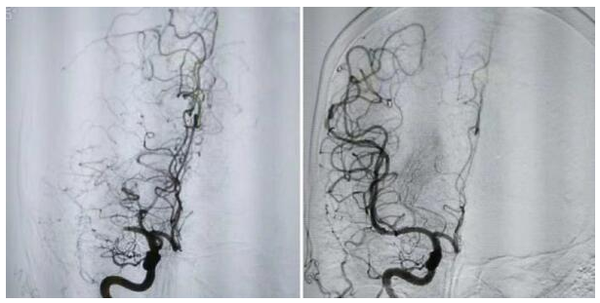

進一步頭顱MR檢查顯示,陳叔右側大腦中動脈閉塞,需立刻進行介入取栓術,上臺5分鐘便恢復腦血流,肌力恢復到4+級。

圖源:暨大附一